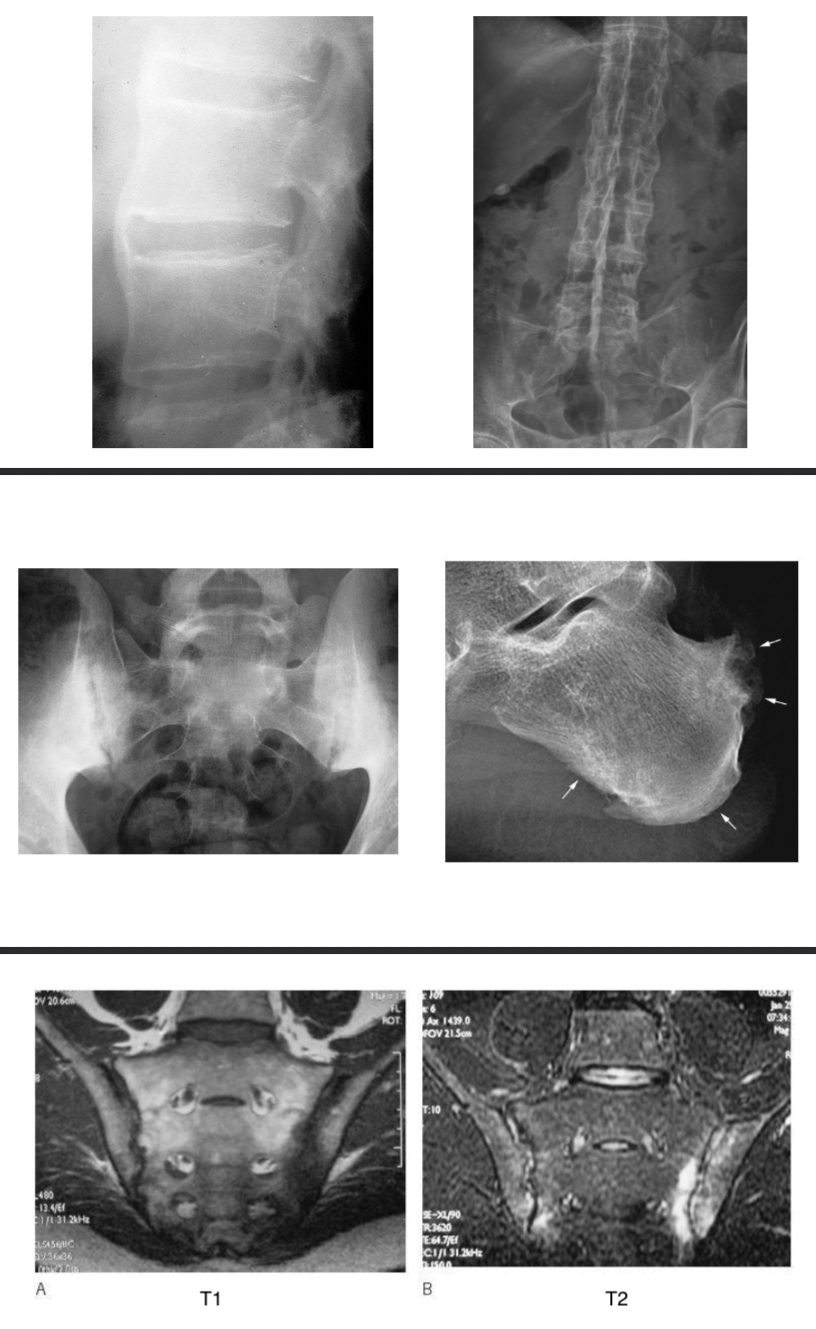

SPONDYLODISCITE INFECTIEUSE

= infection d’un disque intervertébral et des corps vertébraux adjacents

Radio : normale (début) puis décalage radio-clinique 3-4sem

IRM (exam réf diag précoce) : hypersignal du disque et des plateaux vertébraux adjacents, abcès périvertébraux ou épidurite → séquences STIR ou T1 après inj gado / hyposignal en T1

Scanner = si IRM CI, guidage ponction-biopsie discovertébrale

Scintigraphie et TEP-scanner : si IRM CI

SPONDYLOARTHRITES

SPA = ensemble de maladies inflammatoires qui partageant manifestations et terrain génétique

Radio :

rachis cervical, thoracique et lombaire (face + profil) et bassin (face)

syndesmophyte : ossification d'une enthèse vertébrale, spécifique d'une SpA (aspect fin et direction verticale) pouvant aller jusqu'à la « colonne bambou »

sacro-iliite : aspect « flou » des berges articulaires, condensation, érosions pouvant aller jusqu'à la fusion complète

calcanéite inflammatoire

IRM rachis thoraco-lombaire +caro-iliaques = remaniements inflammatoires précédant les modifications radio

Spondyloarthrite ankylosante

syndesmophytes à plusieurs étages

Aspects de « colonne bambou »

Spondyloarthrite de la berge articulaire sacro-iliaque

inflammation des articulations sacro-iliaques